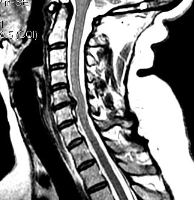

Важно! Если даже после подобной процедуры не станет ясна причина боли в голове, то потребуется дополнительная диагностика в виде МРТ, но уже позвоночника тела человека, а именно его шейного отдела.

При шейном остеохондрозе грыжи не приводят к головным болям, они вызывают корешковый синдром, приводящий к болям и неприятным ощущениям (парестезии, слабости) в руке со стороны грыжи. Редко грыжа сдавливает спинной мозг или нарушает кровоснабжение его участка, приводя к миелопатии. Головные боли при остеохондрозе обусловлены нестабильностью в шейном отделе и болезненным напряжением мышц.

МРТ. Т2-зависимая томограмма. Сагиттальный срез. Грыжа диска.